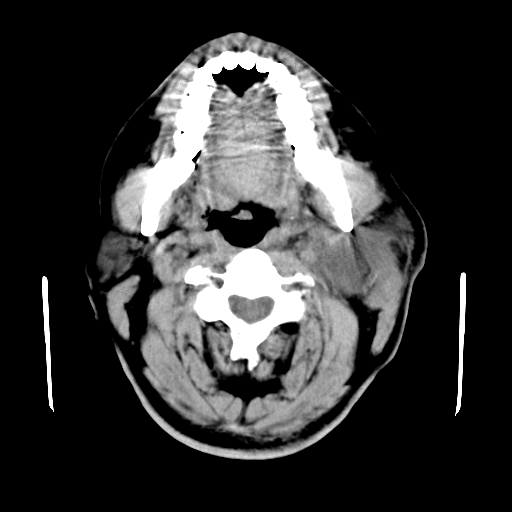

以下是引用卜一在2007-8-6 21:23:00的发言:[br]定位:左侧胸锁乳突肌内侧 颌下腺下后方。特征:弥漫性生长 软组织密度肿块,界限不清,内隐约见低密度坏死。考虑:神经源性肿瘤或血管源性肿瘤。

以下是引用wangzhanshuang在2007-8-6 21:08:00的发言:[br]腮腺混合瘤